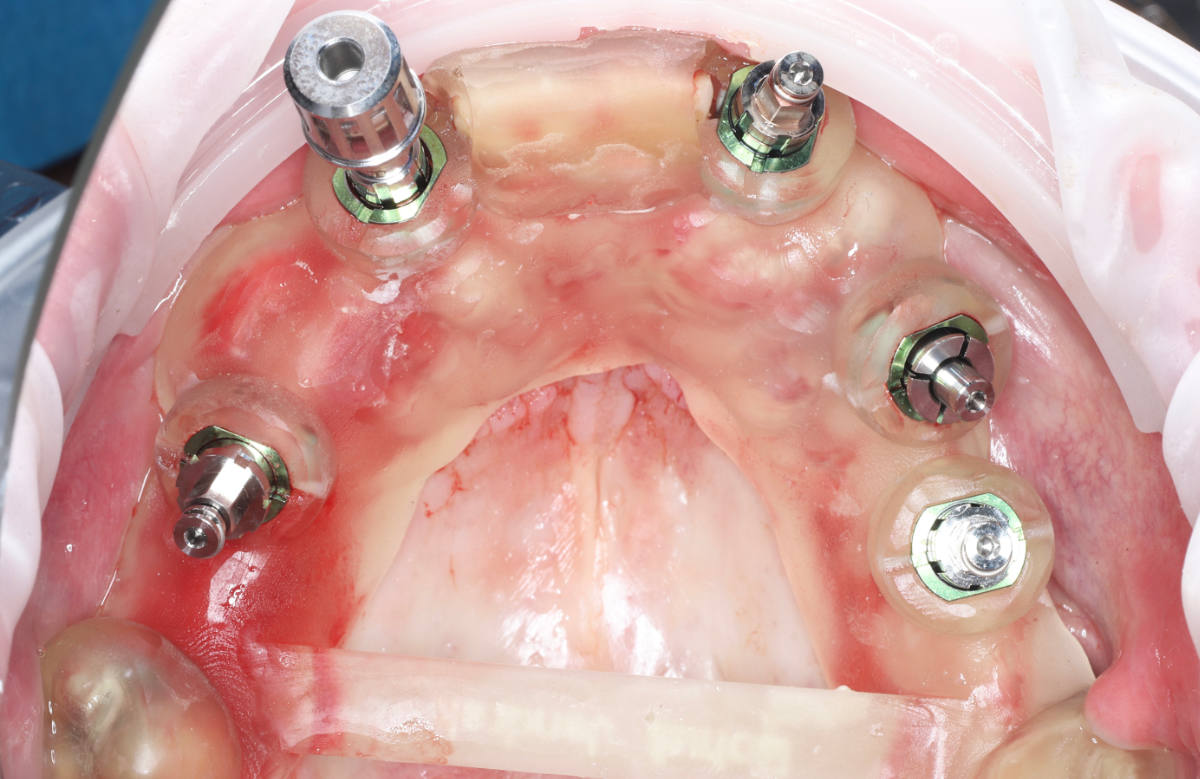

Navigovaná chirurgia, 5 implantátov

Autor práce Dr. Michal Repaši

Zubný technik Vasil Csopej